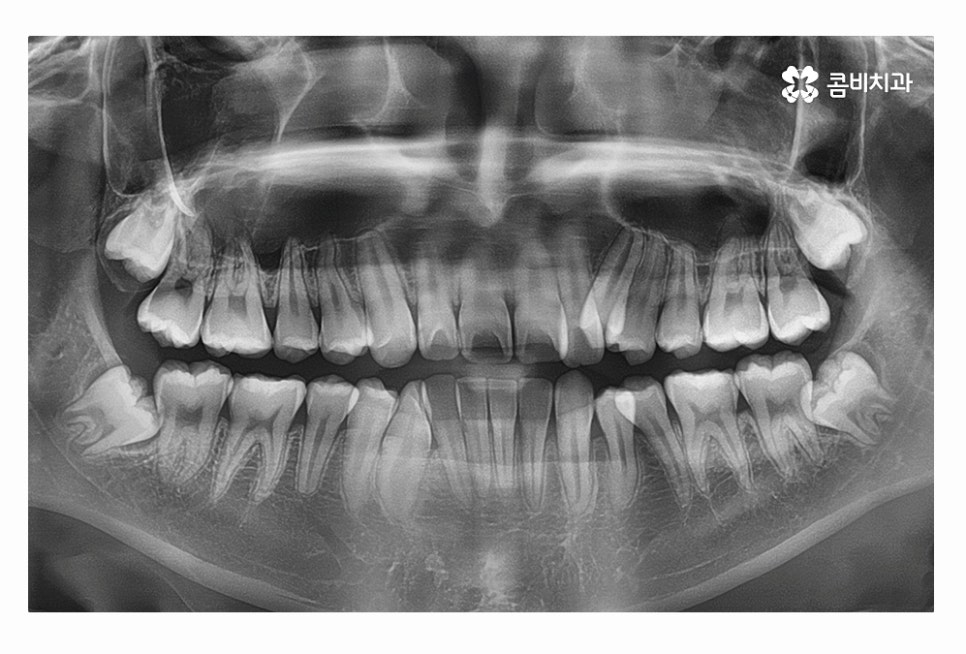

오늘 보시는 환자분의 사례처럼 덧니가 치아끼리 겹쳐 있는 경우에

치아의 이동 공간 확보를 위해서 덧니 발치 필요한 사례였으며

교합과 치아교정 후 얼굴 변화를 고려할 때도 치아교정 과정에서

발치가 필요한 사례였다고 볼 수 있어요.

일반적으로는 송곳니 옆의 작은 어금니를 발치하는

경우가 대부분이며 손상이 심한 치아가 있는 경우에는

손상도가 심한 치아를 발치하는 경우도 있어요